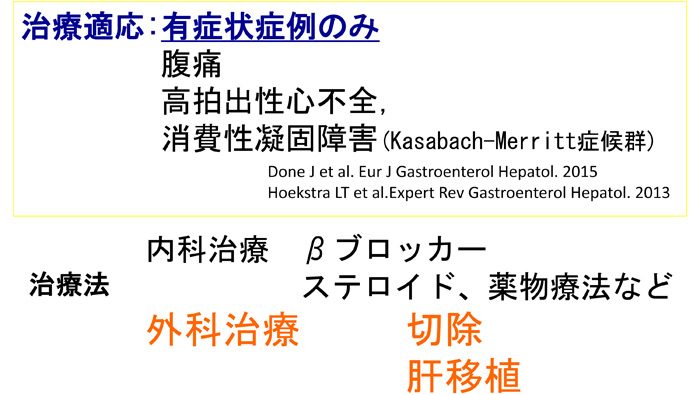

巨大肝血管腫に対する治療戦略(Congenital hepatic hemangioma)

乳児巨大肝血管腫は治療方針において 無症状で経過観察を行うものから、 症状によっては内科的治療の介入や肝移植を含めた外科的治療まで求められる